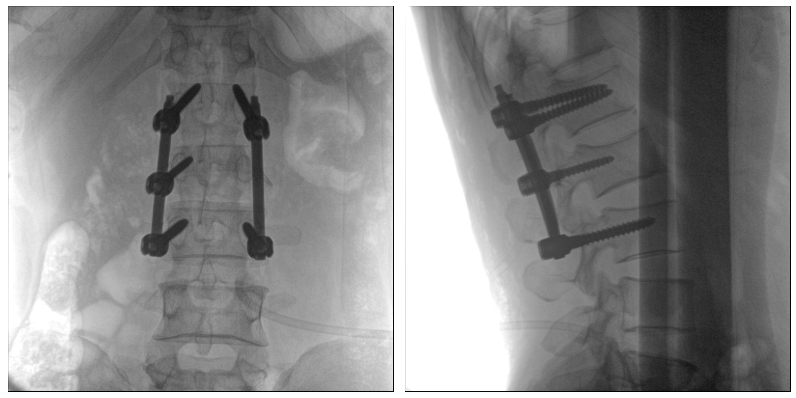

術(shù)中二維影像

從圖中可以看到二維影像能夠提供目標(biāo)區(qū)域在某一個(gè)平面的重疊影像,雖然因?yàn)槿梭w不同組織的密度差異,使得圖像具有較為豐富的信息量,但組織間的相互重疊還是會(huì)出現(xiàn),諸如空間位置等眾多信息在影像中遺失或不可辨認(rèn)的情況,影響了醫(yī)生對(duì)信息的收集與應(yīng)用。